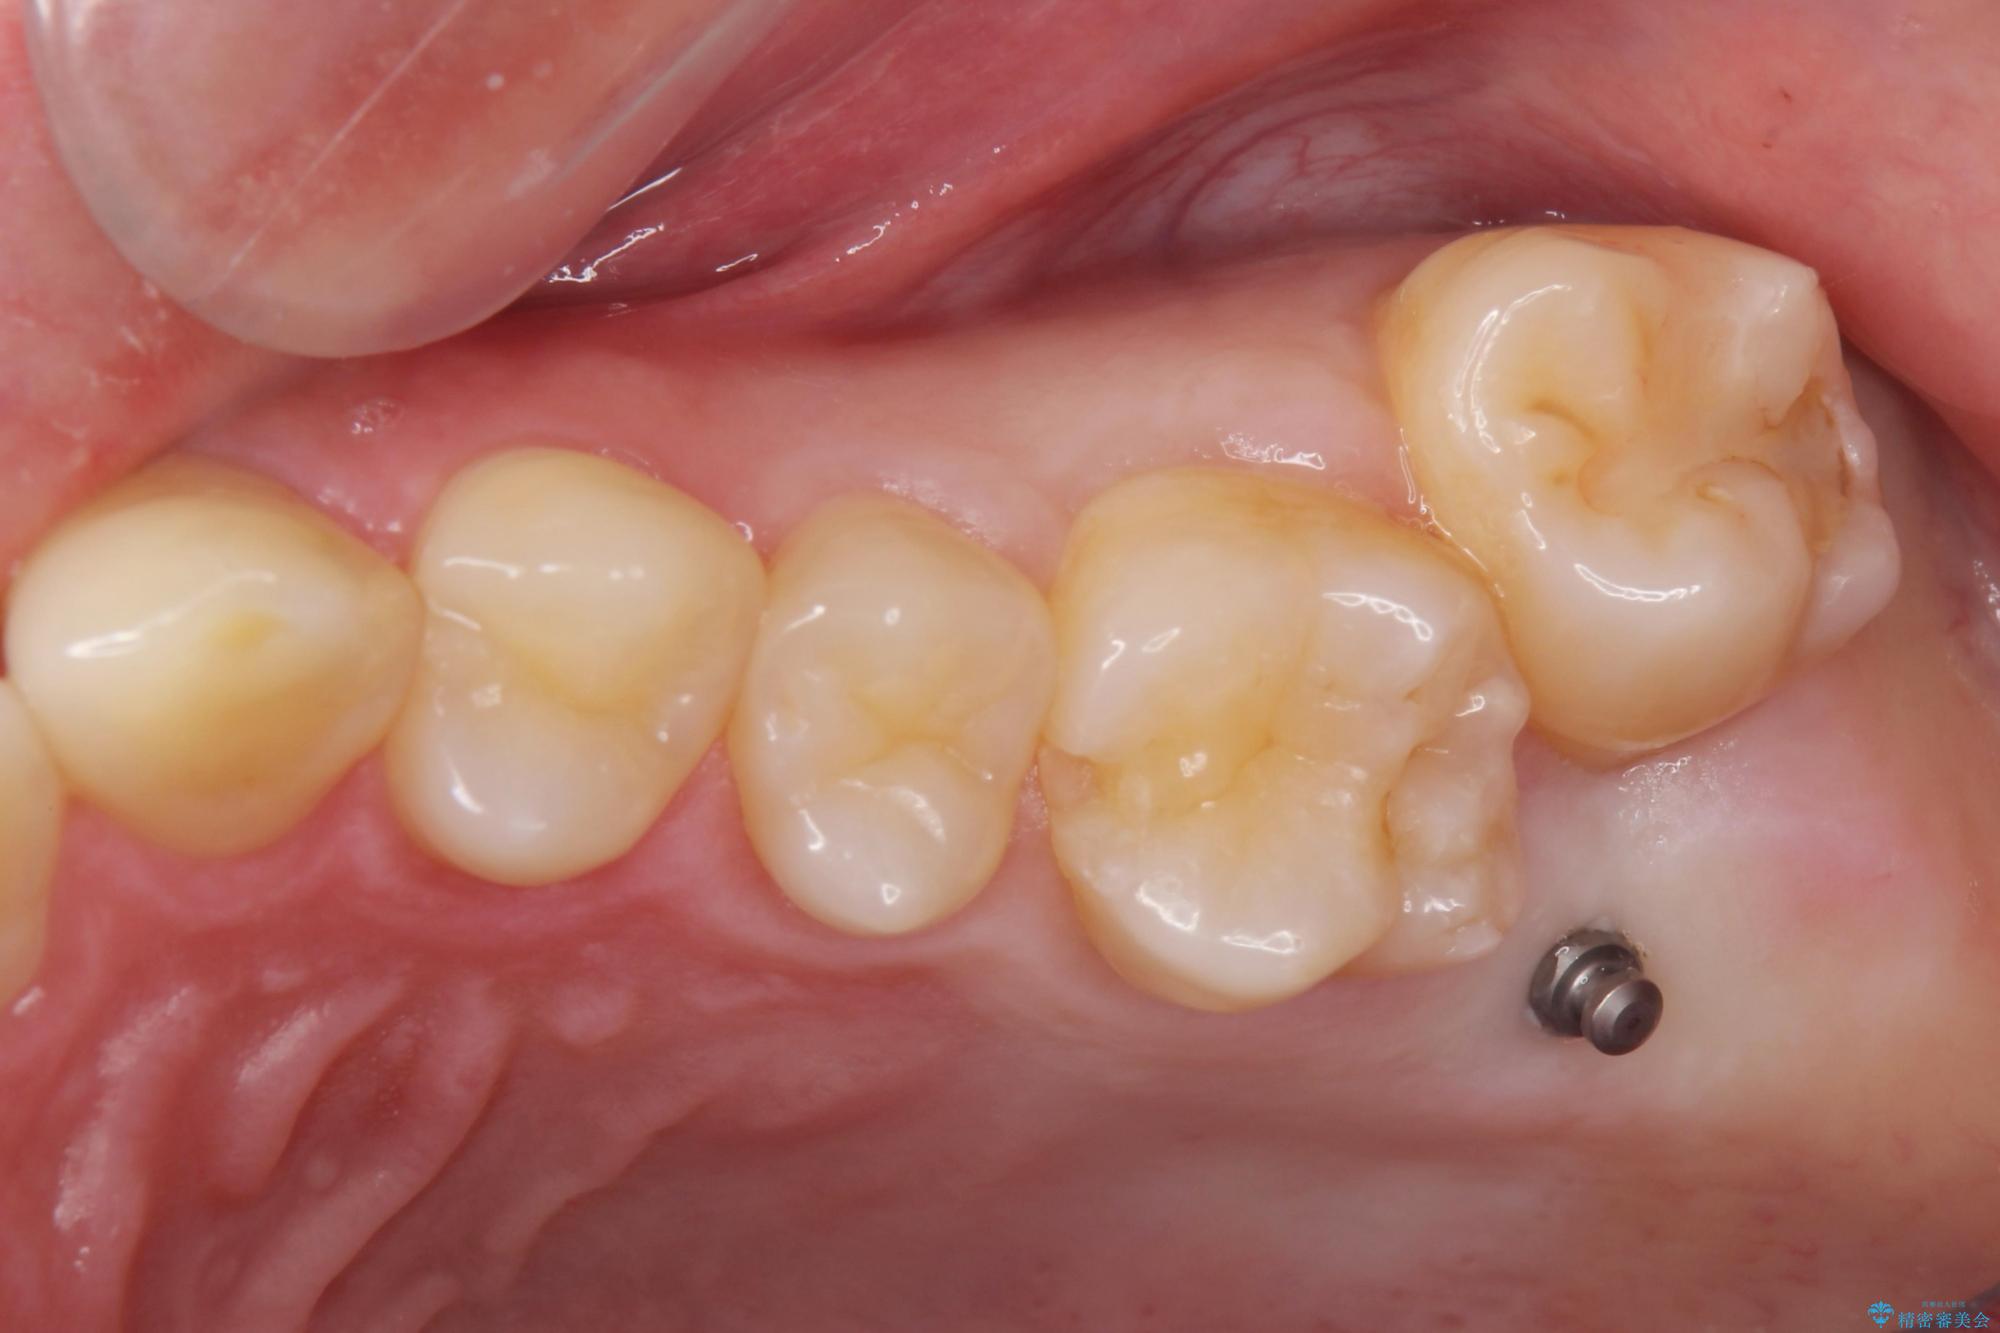

左上の奥歯がシザーバイトがありました。

部分矯正を行いシザーバイトを改善した後、インビザラインで歯列を整えました。